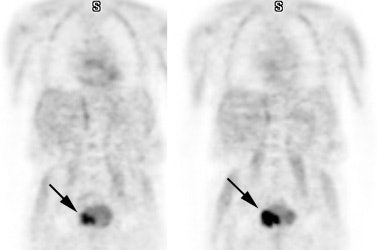

Hyperinsulinemia: The patient below had

a normal glucose level and was injected for an FDG PET

scan. Imaging revealed intense cardiac uptake and a large

about of muscular activity. The findings are consistent

with a hyperinsulinemic state and the patient subsequently

admitted to eating a small breakfast. |